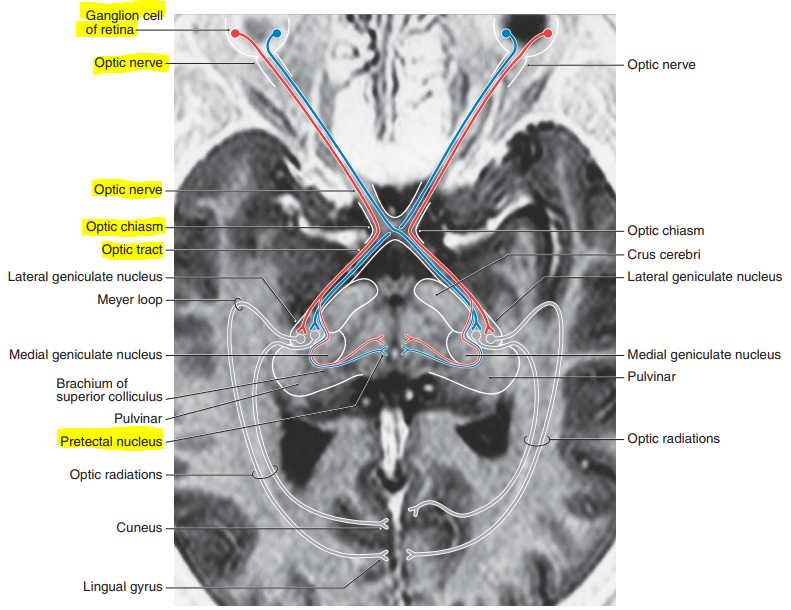

describe the pupillary light reflex circuitry

• shining light into the right eye activates retinal ganglion cells

• the axons of retinal gang. cells form the afferent limb of the reflex arc

• about 50% of the fibers forming the optic nerve stay ipsilateral and continue in the optic tract of the same side, while the other 50% gang. cell axons cross at the optic chiasm and then run along the contralateral optic tract

• not all fibers carrying visual info. synpase in the LGN; some fibers synapse in the pretectal nucleus of the midbrain

• collaterals of axons originating in the pretectal nucleus bilaterally innervate the EW nuclei, which are the accessory nuclei of CN III